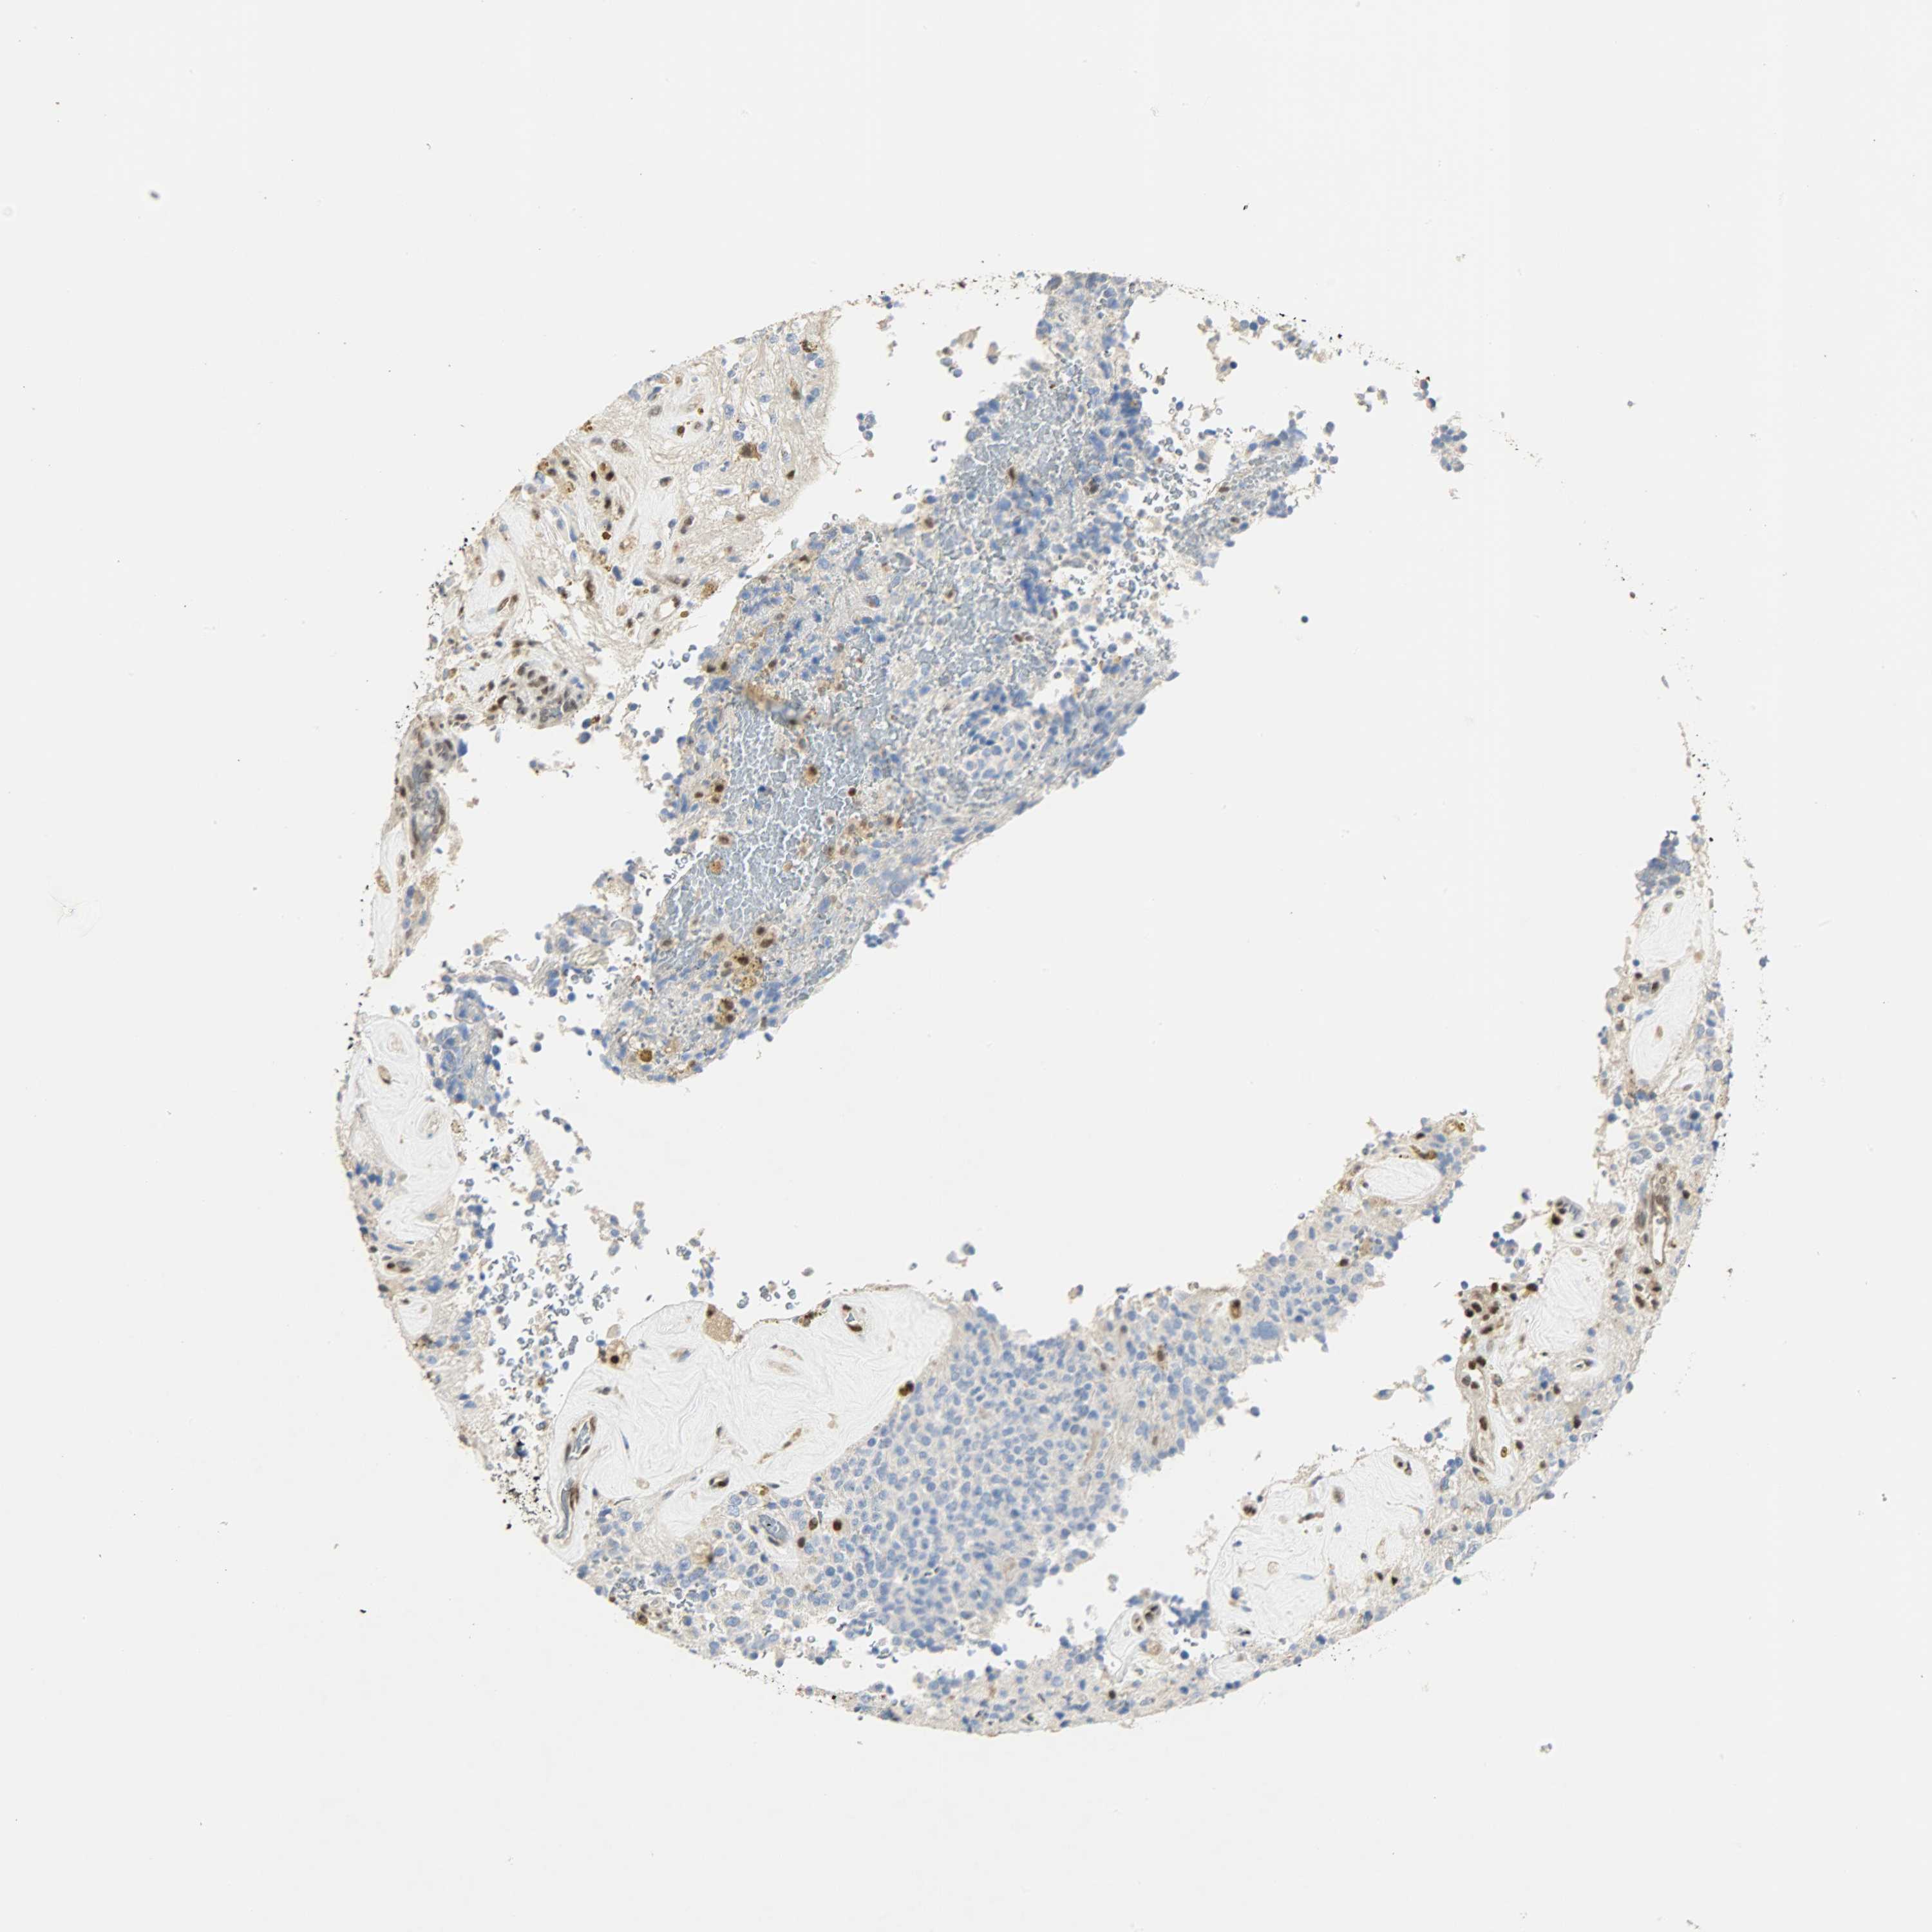

GLIOMA - Protein expressioni

A mouse-over function shows sample information and annotation data. Click on an image to view it in a full screen mode. Samples can be filtered based on level of antibody staining by selecting one or several of the following categories: high, medium, low and not detected. The assay and annotation is described here.

Note that samples used for immunohistochemistry by the Human Protein Atlas do not correspond to samples in the TCGA dataset.

Antibody stainingi

Antibody staining in the annotated cell types in the current human tissue is reported as not detected, low, medium, or high, based on conventional immunohistochemistry profiling in selected tissues. This score is based on the combination of the staining intensity and fraction of stained cells.

Each image is clickable and will lead to virtual microscopy that enables deeper exploration of all samples and also displays staining intensity scores, fraction scores and subcellular localization as well as patient and tissue information for each sample.

Antibody HPA036356

Antibody CAB004986

Antibody CAB017025

Staining

High

Medium

Low

Not detected

Intensity

Strong

Moderate

Weak

Negative

Quantity

>75%

75%-25%

<25%

None

Location

Nuclear

Cytoplasmic/membranous

Cytoplasmic/membranous,nuclear

Glioma, malignant, Low grade

Glioma, malignant, High grade

Glioma, malignant, NOS